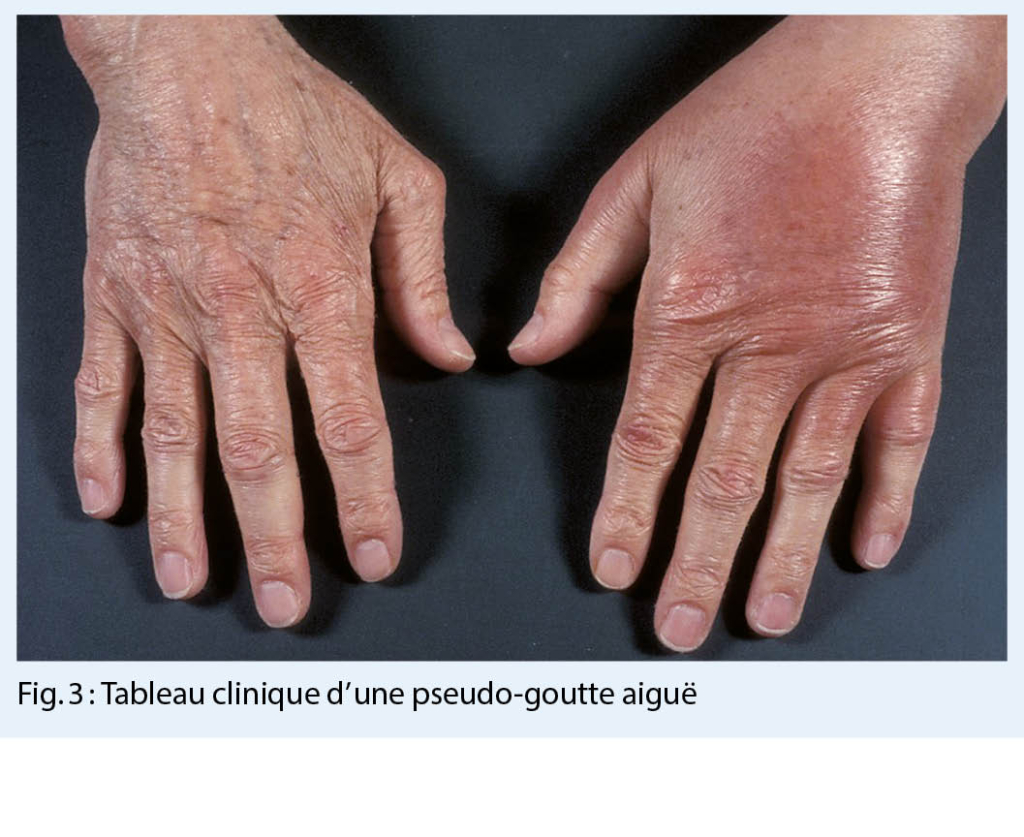

- arthrite aiguë (« pseudo-goutte ») (fig. 3)

En plus du tableau clinique respectif, le diagnostic comprend également la détection microscopique de cristaux de pyrophosphate de calcium dans le liquide synovial ou de calcifications pathognomoniques du cartilage dans la radiographie conventionnelle (fig. 4.) ainsi que dans l’ échographie à haute résolution (ou dans la tomodensitométrie en cas d’ un syndrome de la dent couronnée).